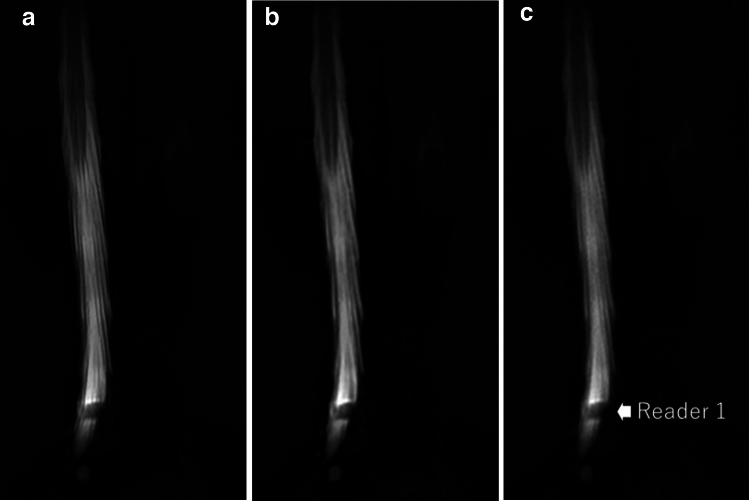

目的:探讨超分辨率深度学习重建(SR-DLR)是否能辅助评价腰椎管狭窄症。材料和方法:在本回顾性研究中,对40例患者(男性16例,女性24例;平均年龄59.4±31.8岁。利用磁共振成像数据,分别通过SR-DLR、深度学习重建(DLR)和传统的零填充插值(ZIP)重建MR脊髓图。三名放射科医生在不了解患者背景数据和MR重建信息的情况下,根据以下项目独立评估图像集:腰椎管狭窄影响的水平数量;和马尾描绘,清晰度,噪声,伪影,和整体图像质量。结果:SR-DLR、DLR和ZIP图像腰椎管狭窄程度的中位观察者间一致性分别为0.819、0.735和0.729。根据所有读者的评价,SR-DLR图像的马尾成像质量、图像清晰度、噪声和整体质量明显优于DLR和ZIP图像(p)。结论:与DLR和ZIP图像相比,SR-DLR提高了腰椎MR脊髓造影的图像质量,并且在评估腰椎管狭窄状态时与更好的观察者间一致性相关。

Material and methods: In this retrospective study, lumbar MR myelography of 40 patients (16 males and 24 females; mean age, 59.4 ± 31.8 years) were analyzed. Using the MR imaging data, MR myelography was separately reconstructed via SR-DLR, deep learning reconstruction (DLR), and conventional zero-filling interpolation (ZIP). Three radiologists, blinded to patient background data and MR reconstruction information, independently evaluated the image sets in terms of the following items: the numbers of levels affected by lumbar spinal stenosis; and cauda equina depiction, sharpness, noise, artifacts, and overall image quality.

Results: The median interobserver agreement in terms of the numbers of lumbar spinal stenosis levels were 0.819, 0.735, and 0.729 for SR-DLR, DLR, and ZIP images, respectively. The imaging quality of the cauda equina, and image sharpness, noise, and overall quality on SR-DLR images were significantly better than those on DLR and ZIP images, as rated by all readers (p < 0.001, Wilcoxon signed-rank test). No significant differences were observed for artifacts on SR-DLR against DLR and ZIP.

Conclusions: SR-DLR improved the image quality of lumbar MR myelographs compared to DLR and ZIP, and was associated with better interobserver agreement during assessment of lumbar spinal stenosis status.